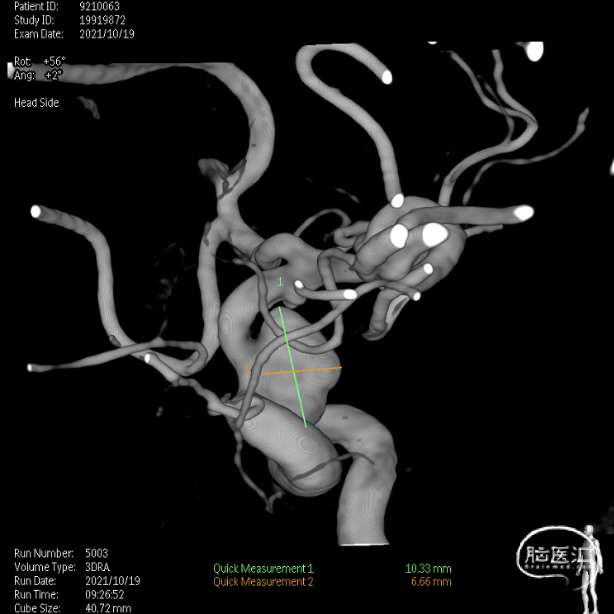

左侧3D

右侧3D

取右侧股动脉为穿刺点,Seldinger法穿刺成功后置入6F鞘。行全脑血管造影显示左侧颈内动脉眼动脉段动脉瘤,约10*7mm大小,瘤颈6.1mm。6F 90长鞘+115cm 6F SKATHI中间导管超选至左侧颈内动脉海绵窦段。